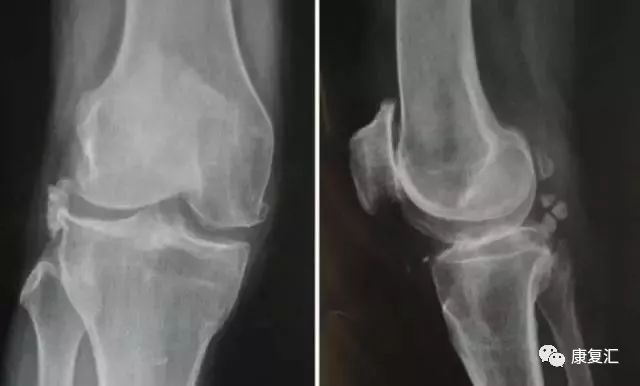

骨关节炎

-

常见(>50岁)

膝关节痛

早期:活动开始时痛、剧院征、上下楼梯时痛、下蹲起立时痛,休息能缓解;

中后期:负重痛、行走痛、夜间痛

短时晨僵 (<20分钟),活动后消失

可有滑膜炎急性发作,关节间隙压痛,活动度减少

关节摩擦音,轻~中度关节积液

X线摄片:负重位前后位、侧位和髌股关节切线位。